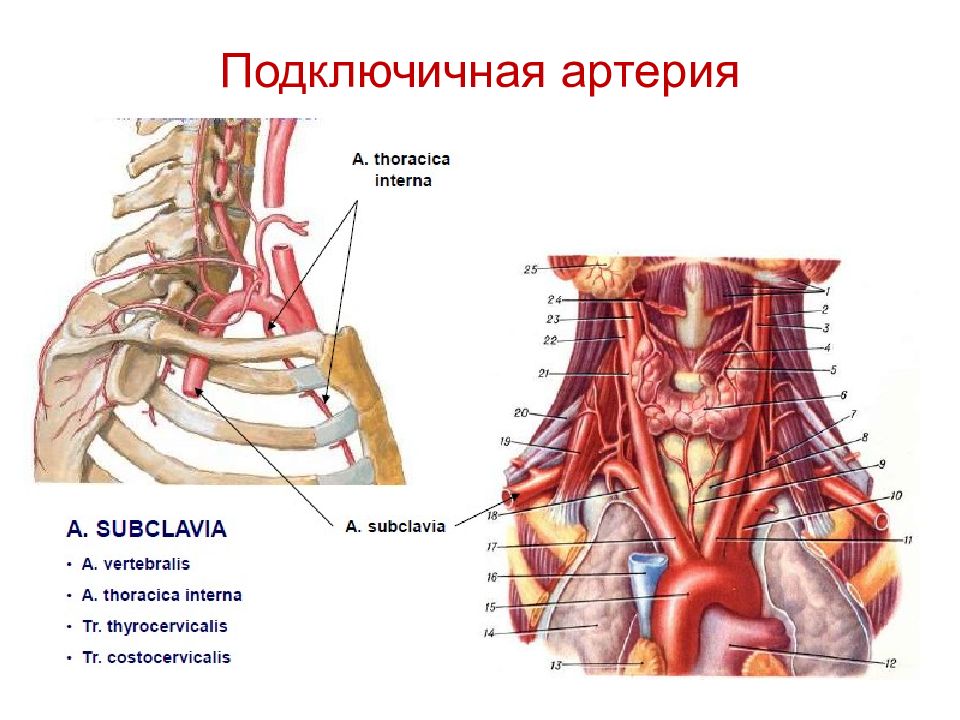

Анатомия внутренней яремной вены: КТ изображения